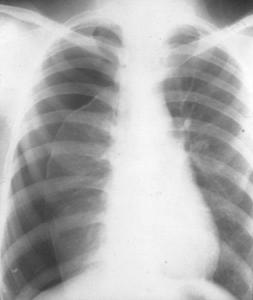

近年來,醫(yī)院胸外科接診了不少青少年患者,主訴大多為突發(fā)性胸悶、胸痛,進行胸片檢查后均提示不同程度的氣胸。并無外傷病史的他們,是如何出現(xiàn)這種癥狀的呢?自發(fā)性氣胸為何總頻頻針對那些身材瘦高的青少年呢?今天,我們就帶大家來認識下它的“元兇”——肺大皰。肺大皰是胸外科一種常見的疾病,是先天性肺局部(常見肺尖部)發(fā)育不良引起的。肺大皰是指由于各種原因?qū)е路闻萸粌?nèi)壓力升高,肺泡壁破裂,互相融合,在肺組織形成的含氣囊腔。肺大皰破裂是青少年自發(fā)性氣胸最常見的病因,發(fā)病率約9/10萬,男女比例約為5:1。由于在青春期生長發(fā)育較快,肺部發(fā)育跟不上胸廓的節(jié)奏,加上瘦高體型的青少年多為扁平胸廓,因此,肺尖部的胸膜腔負壓相對更大,較易形成大皰。形成大皰的肺組織彈力纖維發(fā)育不良,肺泡壁彈性減退,就易在運動、咳嗽、噴嚏時,由于胸腔壓力突然變化時發(fā)生破裂,形成氣胸。首先需要營養(yǎng)均衡,補充一些高蛋白質(zhì)、高熱量、富含維生素的食物,提高機體免疫力。保證充足的睡眠、合理安排作息時間,同時,適當(dāng)?shù)捏w育鍛煉也是必要的。對于肺大皰發(fā)病高危的青少年人群,特別是瘦高體型者,建議青春期體檢時至少進行一次胸部CT平掃檢查(單次CT平掃輻射劑量遠低于國家規(guī)定安全范圍,且能對肺大皰進行快速有效的診斷)。如體檢發(fā)現(xiàn)肺大皰,應(yīng)盡量避免氣壓變化大的運動,如登山、游泳、潛水等。如果出現(xiàn)胸痛、氣短、咳嗽、呼吸不暢等癥狀,要及時到醫(yī)院就診。無癥狀的肺大皰,暫不需要治療。但如出現(xiàn)肺大皰破裂導(dǎo)致的自發(fā)性氣胸,需要根據(jù)氣胸程度,實施胸腔穿刺抽氣或者胸腔閉式引流。持續(xù)的胸腔內(nèi)氣體釋出、反復(fù)自發(fā)性氣胸的發(fā)生以及并發(fā)胸腔、肺部感染,是手術(shù)指征。近年,在肺大皰的手術(shù)治療中,電視輔助胸腔鏡手術(shù)(VATS)逐漸替代了傳統(tǒng)開胸手術(shù)。相較于傳統(tǒng)手術(shù),它有著傷口美觀、手術(shù)時間短、恢復(fù)快、疼痛輕等優(yōu)點。